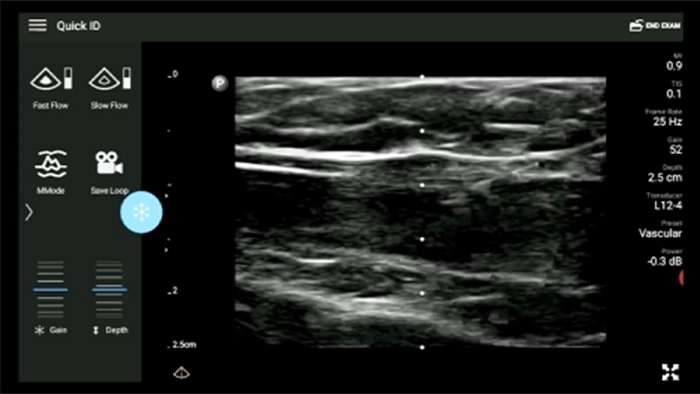

Lumify handheld ultrasound offers images that enhance diagnostic confidence.

See more when it counts

Lumify can help you make real-time decisions with more confidence, from assessment to recovery. Reveal the subtle details of an image, uncover enriched tissue definition with multiple angles and much more.